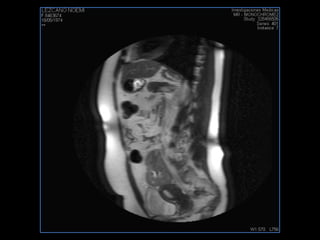

PROTOCOLO abdomen COR T2, AXIAL supresion grasa AX T1 +SAG T2  CON   GADOLINIO :  COR T1+AX T1(DIN) SAT: NO  FASE: RL THK: 6MM  COIL:  GAP: (FACTOR 1.4) 2MM FOV: 40 CM NEX:2 SINCRONIZACION RESPIRATORIA EN 3 O 4 CICLOS ALE

resonancia de abdomen